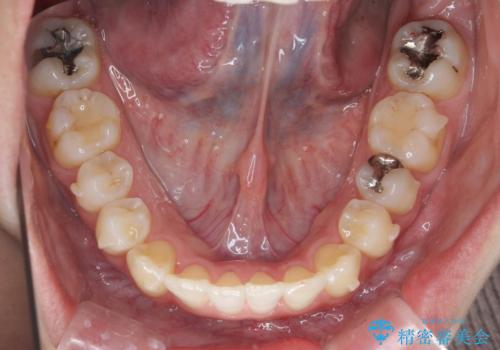

引っ込んだ前歯を並べたい マウスピースと部分ワイヤーのコンビネーション矯正

- 引っ込んで生えてしまっている前歯を並べたい、と矯正治療を希望され来院されました。

まずマウスピース矯正インビザラインシステムで、引っ込んだ歯が並ぶためのスペースを作ったのち、部分ワイヤー矯正を行い短期間での配列を計画します。

マウスピース・ワイヤーそれぞれの長所をうまく活かすことで治療期間の短縮が可能となります。

このように前歯の部分ワイヤーは引っ込んでしまった前歯や がたつきを素早く改善することができます。